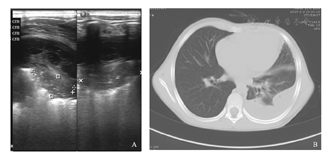

A.肺部超声可见左下肺不张,左侧胸膜增厚,胸腔积液(中量,以纤维素形成分隔为主);B.CT可见左侧后胸壁不规则条带状液性密度影,相邻肺实质受压密度增高,左肺叶间裂增厚,内见少许液性密度影。

肺实变是CAP中重要的超声影像学特点,也是CAP诊断中容易识别的LUS征象,一旦发现有实变征象,再结合临床表现则具有确诊的意义。本研究中80例(46.2%)CAP患儿均见不同程度的肺实变;与之相伴的支气管征是在肺实变中常见到的一种超声图像特征,表现有支气管充气征、支气管充液征,在实时超声下可以见到支气管充气/充液征可以是动态的或是固态的,可以用以鉴别肺实变和合并肺不张[10]。肺不张的超声表现主要有病变区肺实变伴肺搏动、肺滑动征消失及平行排列的支气管充气征等[11,12],而动态空气支气管征的存在排除阻塞性肺不张[13]。LUS中发现大量胸腔积液的存在则提示压迫性肺不张[7];同时,利用积液的不同特点可以辅助判断其性质,如漏出液表现为无回声征象;渗出液可以是无回声,或低回声,或包含各种有回声的物质(浮游生物征),或有分隔[14](图4)。